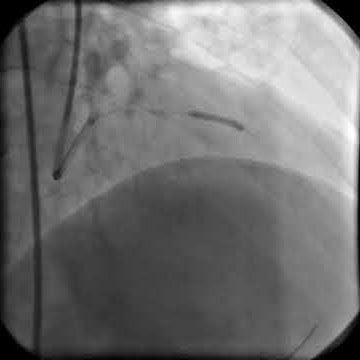

Здоровье под контролем: использование баллонов для стентирования